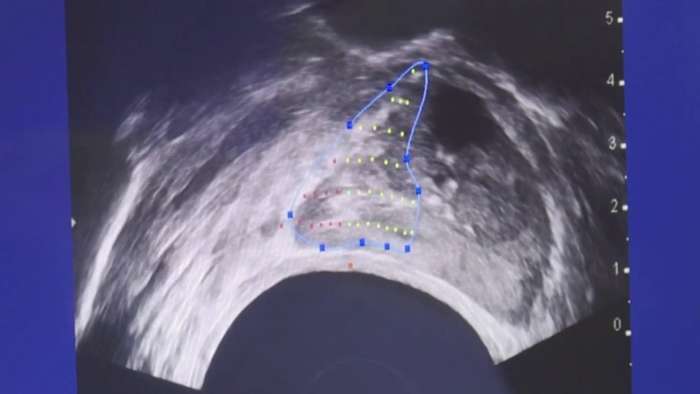

연구에 따르면 전립선암 환자의 60%가 치료를 받지 않고도 동일한 수명을 유지하고 있습니다. 이는 많은 환자들이 치료의 부작용을 피하고자 하는 선택을 하고 있음을 시사합니다....